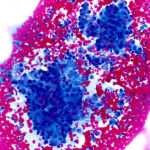

Two Modes of Operation

Deposit and stain mode produces two monolayer slides, one unstained and one Diff-Quik(R) stained in 70 seconds.

Stain only mode Diff-Quik(R) stains touch preps and hand prepared smears for immediate high quality immediate staining in 45 seconds.

Adaptable workflow lets you switch between full slide preparation or stain alone, addressing different biopsy needs automatically.